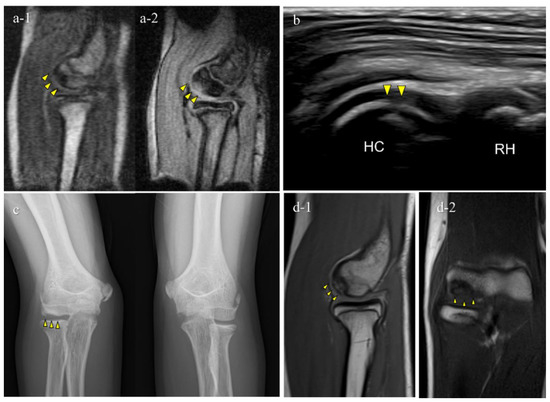

Diagnostics October 2022 Browse Articles